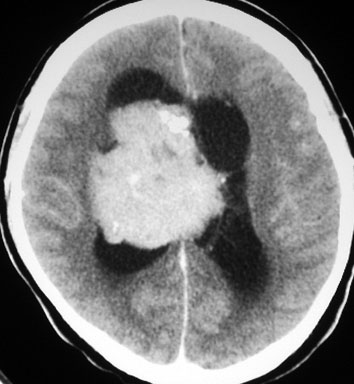

20代の男性の神経細胞腫です。側脳室の中のとても大きな腫瘍です。上段はガドリニウムという造影剤を入れた時のMRIです。下段の中央はCTですが,石灰化が見られます。脳外科の先生には,この脳室内腫瘍は一見transcallosal approach(経脳梁到達法)という手術で取れるように見えるかもしれませんが,そうではなくて,脳室の壁とくに上壁と側壁にくっついているのでなかなか取れません。この患者さんの場合は右の頭頂葉というところからtranscortical approach(経皮質到達法)で全摘出しました。後遺症もなく再発もなく術後10年が過ぎています。全部とれれば治ってしまう腫瘍です。